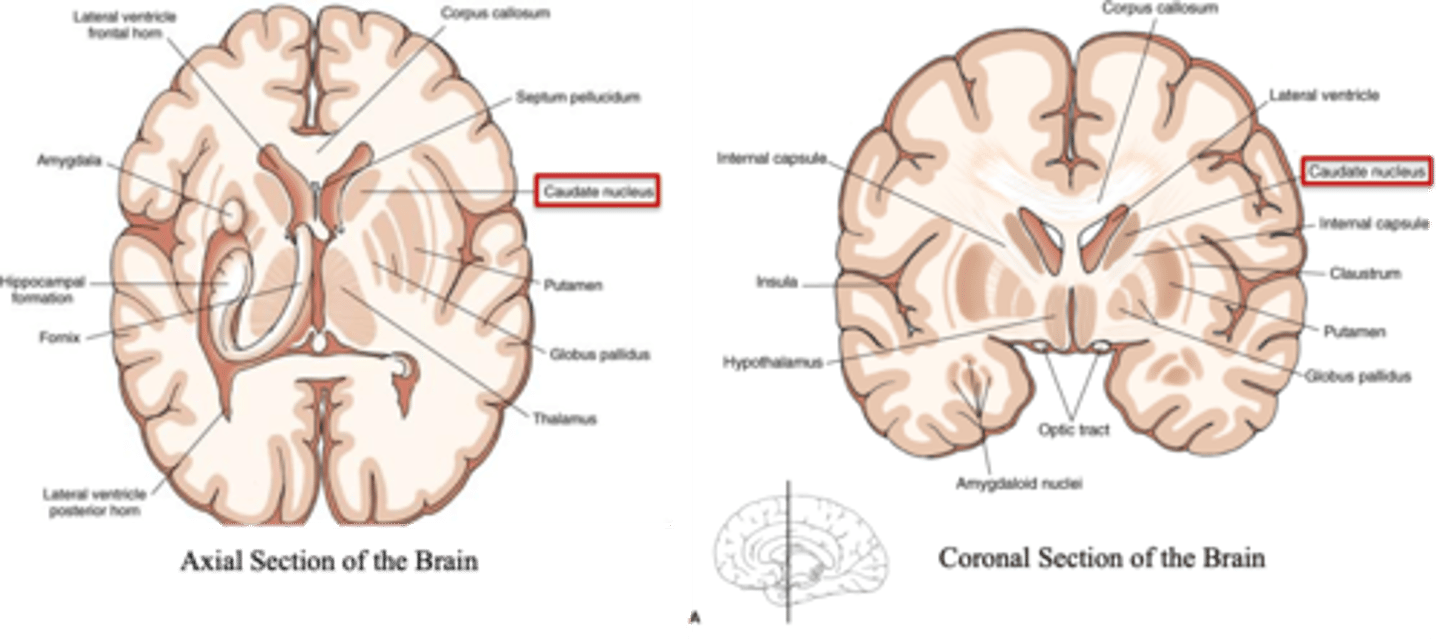

what are the 3 parts of the basal ganglia? what runs between them?

1. caudate nucleus

2. putamen

3. globus pallidus

internal capsule

what part of the basal ganglia is the C-shaped structure that is most medial?

caudate nucleus

what part of the basal ganglia is medial to the putamen?

globus pallidus

the putamen and globus pallidus of the basal ganglia are collectively called the _______________ nucleus

lentiform